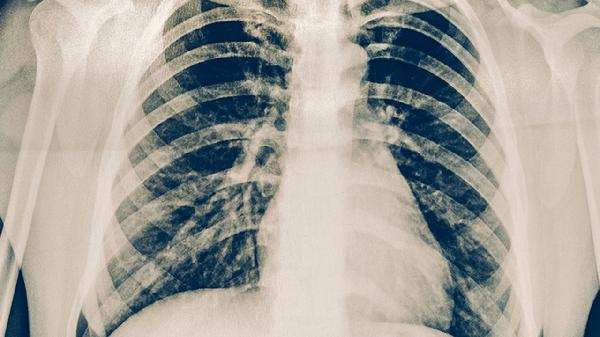

肺心病患者日常保养需结合生活方式调整、饮食管理和医疗监测,主要有戒烟限酒、规律氧疗、适度运动、控制盐分摄入、定期复查五项措施。